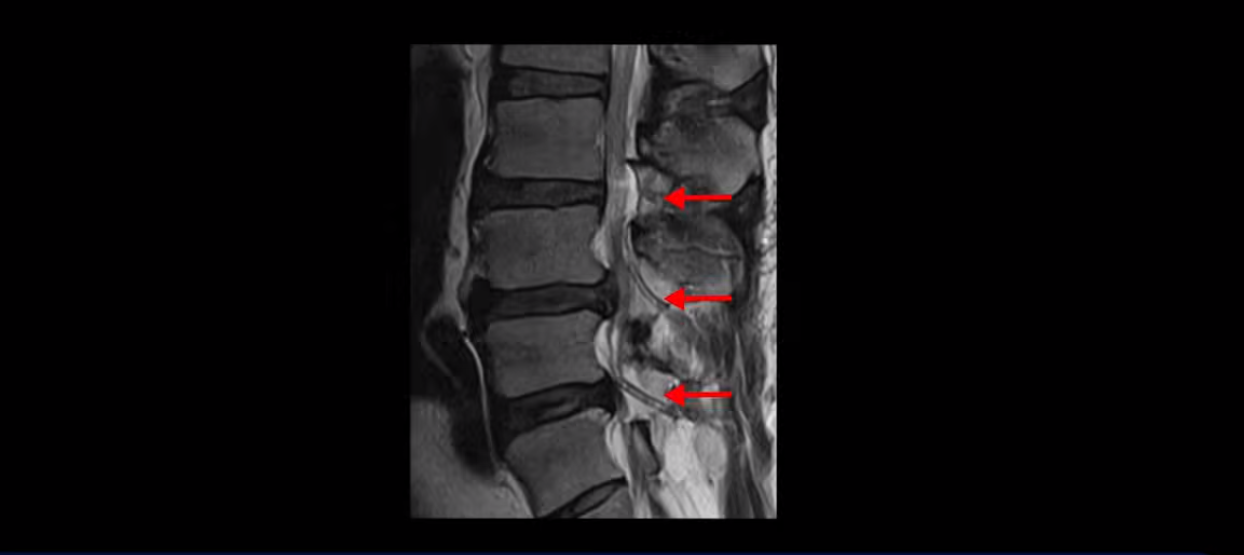

목 5번 6번을 보면 디스크가 심하게 밀려 나와서 척수 신경을 누르고 있습니다.

척수 신경이 눌려서 손상된 사인이 하얗게 보입니다. 이걸 경추척수증이라고 합니다.

척수 신경이 눌리고 손상되니까 양쪽 손과 양쪽 다리 모두에 증상이 생깁니다. 양손에 힘이 빠지고 젓가락질이 힘들고, 단추 끼우기도 어려워지고 다리에 힘이 빠지니까 걷기도 힘들어집니다. 양손과 다리의 감각도 떨어지고요. 그래서 이 환자분은 수술하더라도 목 수술을 해야 하는데, 엉뚱하게도 허리 수술을 받습니다. 처음에 병원에 갈 때 허리도 원래 많이 아팠다고 하니까 그 병원에서 목 검사와 허리를 함께 검사해 보고 허리 협착도 심하니까 허리 수술을 먼저 하자고 합니다. 그래서 허리 세 마디를 수술했습니다.